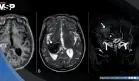

Los marcadores serológicos finalmente revelaron la verdad: los anticuerpos anti-ADN de doble cadena y antinucleares estaban elevados 10 y 6 veces respectivamente, confirmando el diagnóstico de lupus eritematoso sistémico.